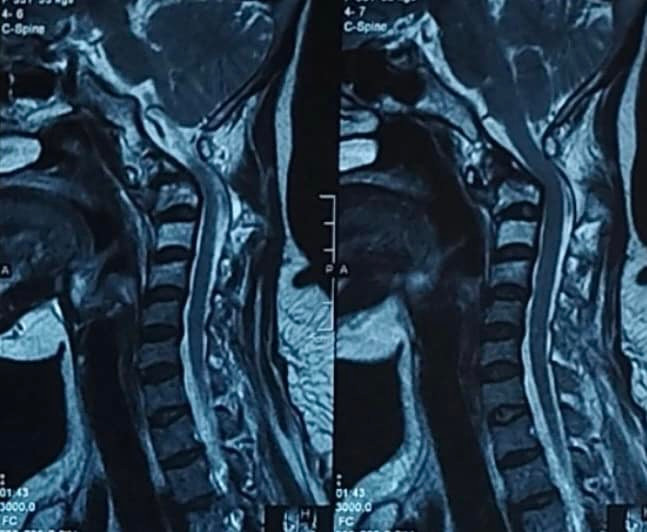

Bệnh nhân Phạm Thị Thanh V. 54 tuổi, quê tại huyện Vĩnh Tường, tỉnh Vĩnh Phúc được chẩn đoán ung thư phổi di căn cột sống cổ cao C1, làm hủy thân đốt sống cổ, gây đau và tê tay. Bệnh nhân được các bác sỹ bệnh viện K hội chẩn, điều trị đa mô thức giúp kiểm soát bệnh toàn thân, cũng như điều trị khối u di căn vị trí nguy hiểm là cột sống cổ cao.

Với chẩn đoán ung thư phổi giai đoạn muộn; bệnh nhân V. đã được điều trị hoá chất, trong quá trình điều trị, bệnh tiến triển, di căn lên các đốt sống cổ C1, C2.

Được nhận định là ca bệnh phức tạp, các chuyên gia hóa chất và xạ trị cũng như phẫu thuật của bệnh viện K đã hội chẩn rất kỹ càng, bác sỹ đánh giá trường hợp bệnh nhân V.cần được điều trị phối hợp nhiều chuyên khoa: đầu tiên bệnh nhân cần được điều trị xạ trị cột sống nhằm làm giảm chèn ép, cột sống được cố định tạm thời bằng nẹp cổ, đồng thời được điều trị hóa chất toàn thân.

Sau 1 tháng, tình trạng khối u phổi được kiểm soát tốt, khối u cột sống cổ cao đã co nhỏ, lúc này bệnh nhân được tiến hành cố định cột sống cổ nhằm giải quyết tình trạng mất vững của người bệnh, phòng ngừa nguy cơ liệt tứ chi.